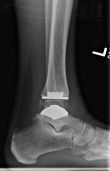

New Findings in #JBJS: Smoking, Depression (But Not Obesity) Adversely Affect Outcomes after TAA https://t.co/JflAgSzyaJ @AOFAS pic.twitter.com/Eodq2AmO96